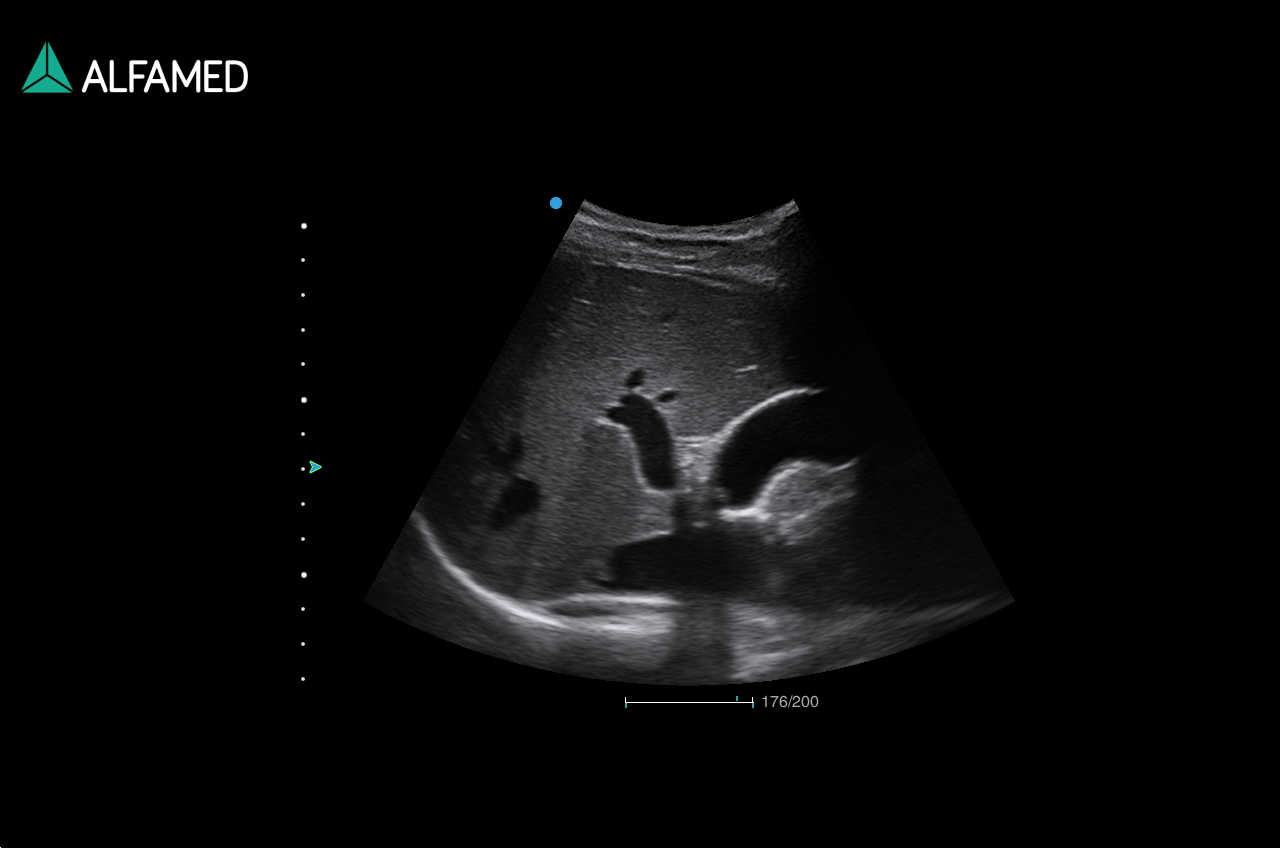

Dotado de softwares avançados e transdutores específicos, o Magnus X5 apresenta alta versatilidade para imagem geral e excelente performance, principalmente, nos exames de cardiologia avançada e obstetrícia.

- 4D Pro (Qcut/Any Cut, nSlice)

- 4D Lumi